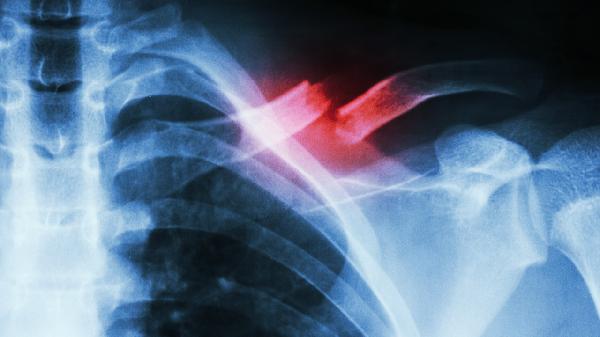

成人粉碎性骨折、骨折端移位超过2厘米或合并臂丛神经损伤时需手术内固定。开放性骨折或伴有锁骨下血管损伤属于绝对手术指征,通常采用锁骨解剖型钢板或髓内钉固定。术后早期需悬吊保护,6周后逐步开始被动活动。手术禁忌症包括局部感染未控制、严重骨质疏松无法有效固定,以及合并危及生命的复合伤需优先处理等情况。